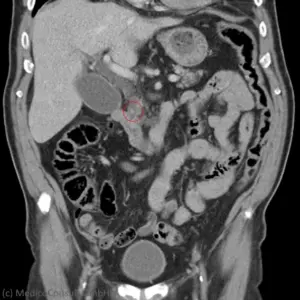

Röntgenuntersuchung

Röntgenologisch stehen eine orale oder intravenöse Cholezystographie, eine Computertomographie (CT) und eine MRCP zur Verfügung. Sie kommen vor einer laparoskopischen Cholezystektomie in Frage, wenn eine Steinbesiedlung der Gallenwege ausgeschlossen werden soll. Am sensitivsten sind das Kontrastmittel-CT und das MRT. Die Sensitivitäten erreichen jedoch nicht die einer Endosonographie. 21

→ Zur Computertomographie (CT) der Leber siehe hier.